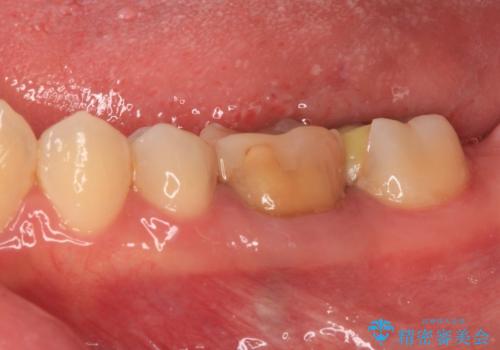

一番奥の歯は詰め物が脱離しており、仮詰め材が詰まっており、手前の歯は根管治療後に樹脂で固めたままの状態でした。

手前の歯を仮歯に置き換えるとともに、一番奥の歯のむし歯治療を行うこととしました。